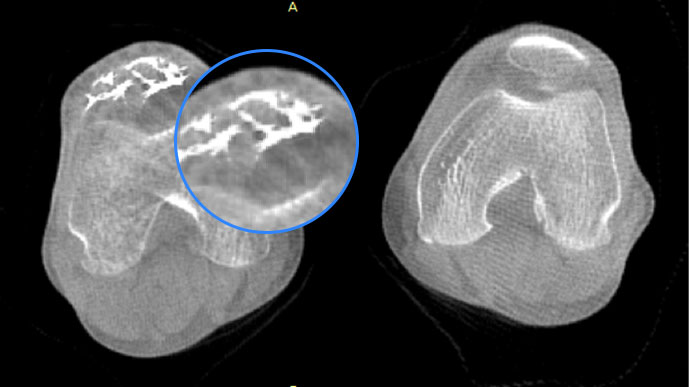

膝关节

FOV 250mm

FOV 350mm

关闭金属伪影校正

开启金属伪影校正